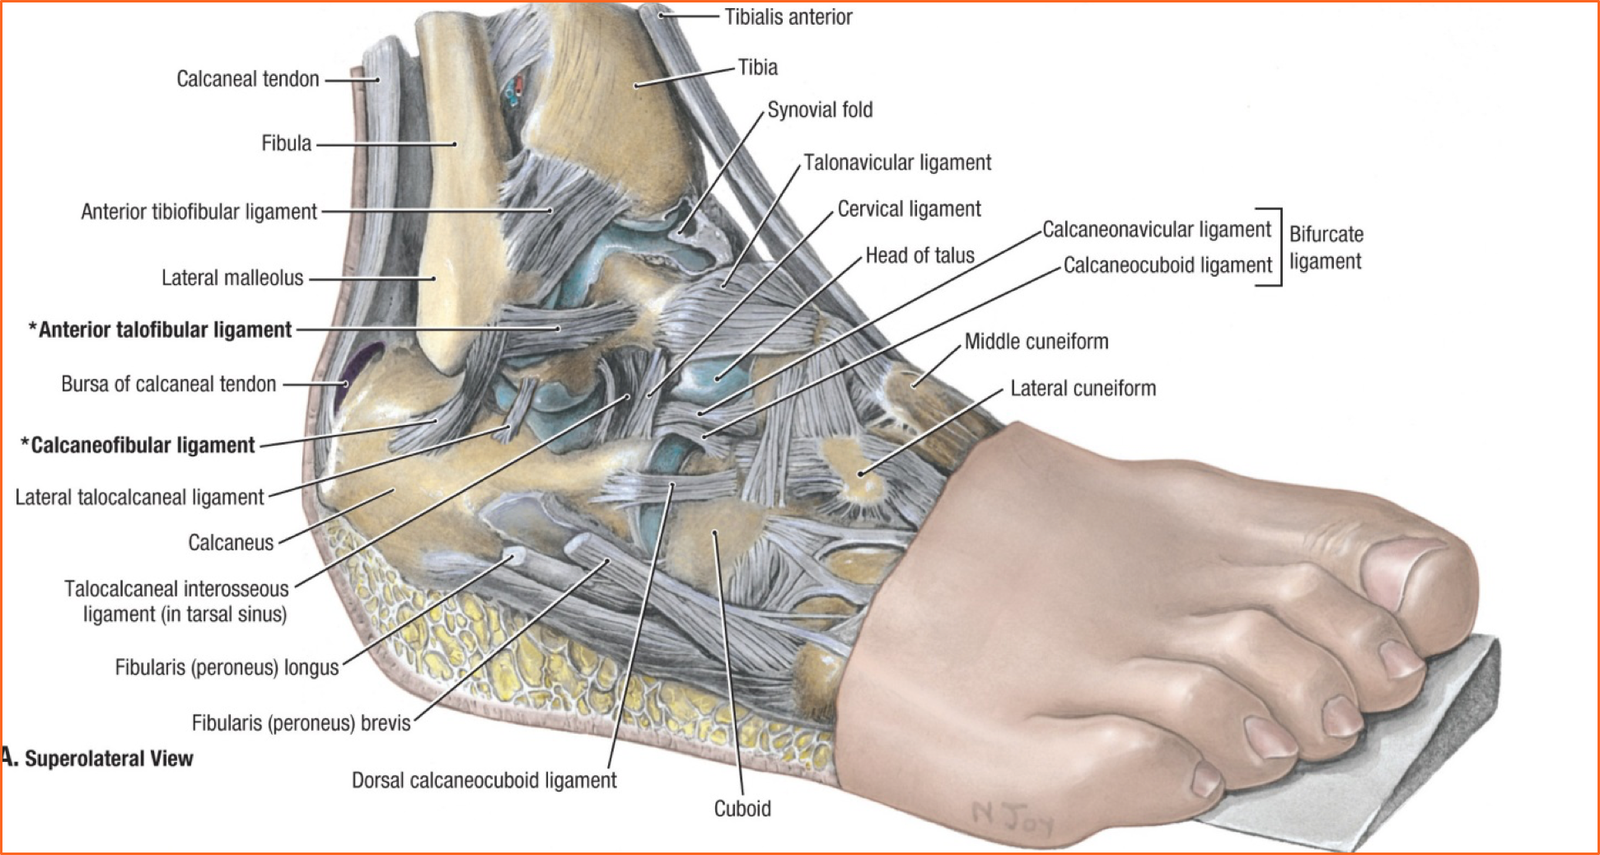

Анатомия голеностопа: Сухожилия и их строение